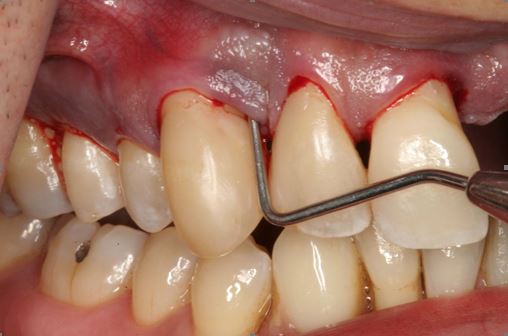

Dziąsła i przyzębie w stanie zapalnym.

Zapalnie zmienione dziąsło jest zaczerwienione i obrzęknięte, niekiedy sine. W początkowych stadiach choroby nie ma bólu. Pacjenci często mówią: nic mnie nie boli, więc chyba jest w porządku. Otóż nie, ból pojawia się dopiero w zaawansowanych a nawet terminalnych stadiach choroby. Od początku natomiast występuje krwawienie. Pamiętajmy więc, że krwawienie pojawiające się przy szczotkowaniu i nitkowaniu zębów jest ważnym sygnałem alarmowym i nie wolno go zaniedbywać. Nawet przy niewielkim podrażnieniu, np. przy myciu, sondowaniu szczeliny dziąsłowej. Powoli stan zapalny nasila się, powstają drobne mikroowrzodzenia nabłonka szczeliny dziąsłowej. Przy dalszym nasileniu choroby zaczynają się formować ropnie przyzębia – definicja: zlokalizowany ropny stan zapalny tkanek przyzębia. Ropnie mogą być pojedyncze i mnogie, ostre, lub przewlekłe, ze względu na lokalizację: dziąsłowe, przyzębne, okołokoronowe i okołowierzchołkowe. Ropnie formują się zwłaszcza tam, gdzie są pionowe ubytki tkanki kostnej, otwarte rozwidlenia korzeni (rozwidlenia korzeni występują u zębów wielokorzeniowych). Znaczącą rolę odgrywają pogorszenie higieny jamy ustnej, współistniejące choroby. Rozległe ropnie powoduje szybką i rozległą destrukcję tkanek przyzębia, w tym kości, co często skutkuje utratą zęba, zwłaszcza u osób z zaawansowaną chorobą i ubytkiem kostnej otaczającej zęby. Ważna uwaga! Rozważmy sytuację: pacjent zauważa krwawienie z dziąseł przy zabiegach higienicznych, przy posiłkach. Gdzie kierujemy pierwsze kroki? … Do Internetu. Korzystanie z porady dr Google może / musi nas jednak ukierunkować na zakup pasty do zębów, prawdopodobnie tej, która jest aktualnie najlepiej pozycjonowana w wynikach wyszukiwania. Jeżeli składniki farmakologiczne zawarte w paście stłumią krwawienie, może to uśpić nasza czujność i odwlec w czasie wizytę u lekarza stomatologa. W tym czasie choroba, pomimo braku objawów uchwytnych przez pacjenta, przy zmniejszonym krwawieniu, rozwija się w ukryciu. Zmniejsza to nasze szanse na szybkie podjęcie skutecznej terapii.